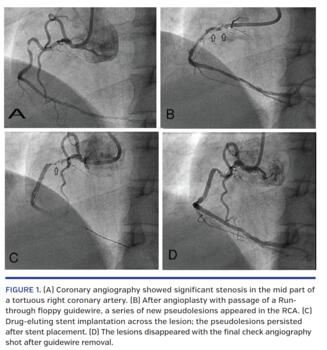

A 40-year-old male was admitted to the cardiology department with inferior-wall myocardial infarction. He was taken to the cardiac catheterization laboratory with an intent for primary percutaneous intervention. During coronary angiography, he was found to have significant stenosis in the mid part of a tortuous right coronary artery (Figure 1A). Percutaneous transluminal coronary angioplasty was decided upon and a Runthrough floppy guidewire (Terumo) was passed. There was immediate appearance of a series of new “pseudolesions” in the right coronary artery (Figure 1B and Video 1). A drug-eluting stent was placed across the lesion with guidance of anatomical landmarks. The pseudolesions persisted after stent placement (Figure 1C). The lesions disappeared with the final check angiography shot after removal of the guidewire (Figure 1D).

Accordion effect or concertina effect — also known as “crumpled coronary” — is an uncommon occurrence during coronary angioplasty. It occurs due to straightening of a tortuous coronary artery along its luminal axis by relatively stiff coronary equipment due to invagination of excess tissue. It usually has no major clinical sequelae and should be differentiated from spasm, dissection, and thrombosis, which require special management.